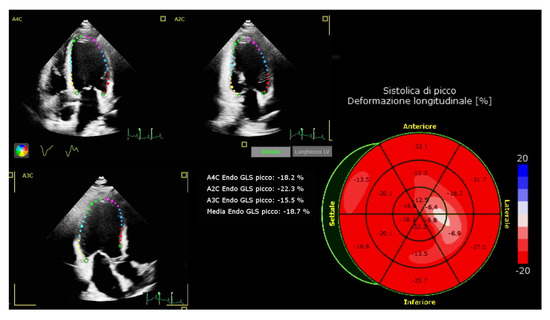

| LV GLS, %, mean ± sd | −18.0 ± 1.8 | −19.5 ± 2.1 | −1.4 ± 1.1 | <0.001 |